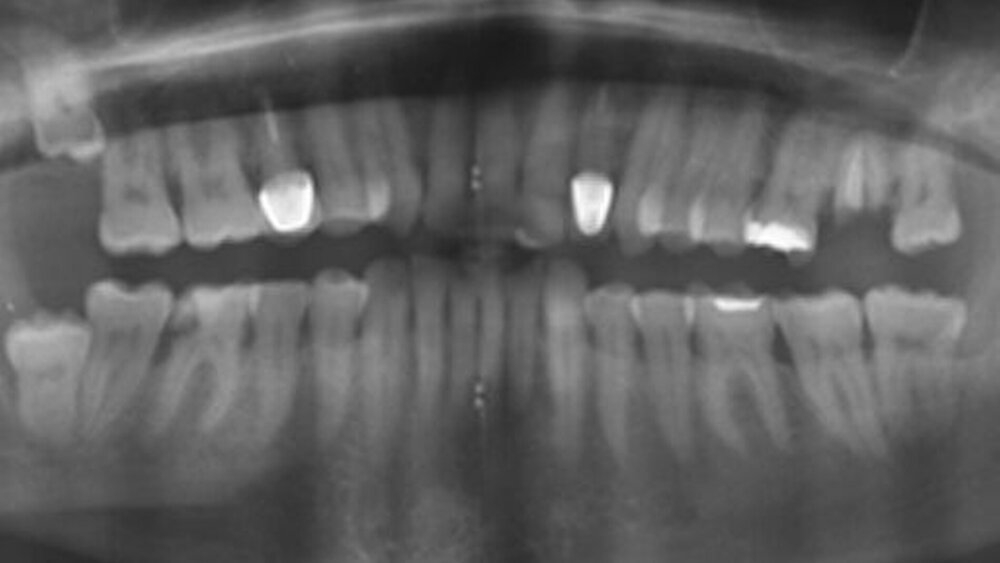

Ein 67-jähriger Patient stellte sich mit einer seit drei Wochen größenprogredienten rot-bräunlichen Schwellung in regio 48 bei seinem Hauszahnarzt vor. In der alio loco angefertigten Panoramaschichtaufnahme zeigte sich eine unscharf begrenzte Aufhellung perikoronal um einen teilretinierten Zahn 048 (Abbildung 1). Daraufhin wurde der Patient an die Klinik für Mund- Kiefer- und Gesichtschirurgie der Uniklinik Bonn überwiesen.

Anhand der klinischen Beurteilung wurde die Verdachtsdiagnose eines Plattenepithelkarzinoms gestellt. Differenzialdiagnostisch kam eine Epulis in Betracht. Zur Beurteilung der Befundausdehnung sowie zur Planung der weiteren Therapie wurde ein CT des Halses mit Kontrastmittel im Rahmen des Stagings durchgeführt. Im CT konnte das Ausmaß der Osteolysen ermittelt werden. Zu dem Zeitpunkt hatte keine Arrosion der Kortikalis stattgefunden (Abbildung 3). Darüber hinaus zeigten sich zahlreiche prominente und insbesondere rechtsseitig vergrößerte zervikale Lymphknoten, welche als metastasenverdächtig eingestuft wurden (Abbildung 4). Aufgrund der unklaren Dignität des Befundes erfolgte zur histologischen Diagnosesicherung die ambulante Probeentnahme in regio 048.